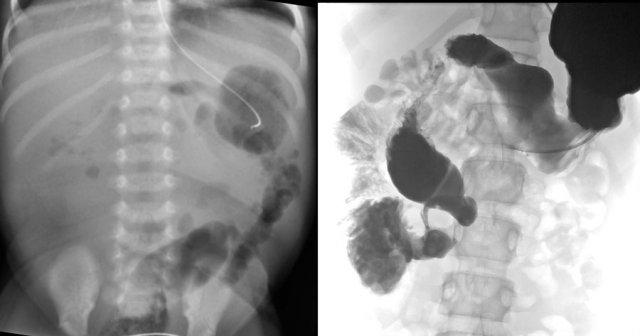

Phim X-quang sẽ cho thấy nhiều quai ruột giãn và không có khí trong đại tràng như hình ảnh bên trái.

Thụt tháo đại tràng sẽ thấy hình ảnh đại tràng nhỏ với thuốc cản quang lấp đầy kết thúc dạng túi cùng ở hồi tràng (mũi tên trên hình bên phải).